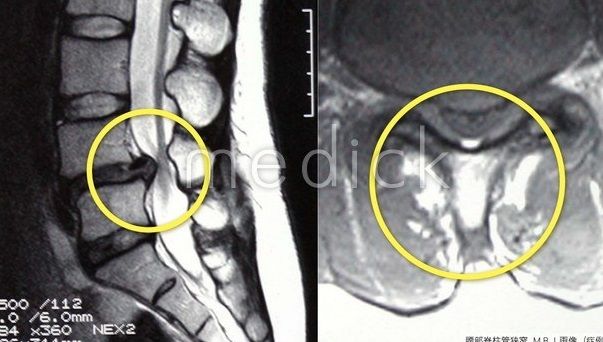

おまけ 脊椎狭窄症と膝関節炎を理解する2

レントゲンやなどの画像に異変のある方で症状が出るのは3割程度

という現実を考えるとき、 7割は何処に行ってしまったのだろうか?

痛みとしての症状は画像解析だけで捕えると3割しか当てはまらないのだから、研究グループは 「7割は別物として見直すべきで、症状が出ないからと放置してはいけない」 と言いって当然だと言う事です。

画像では同じなのに痛まないのは何故か?